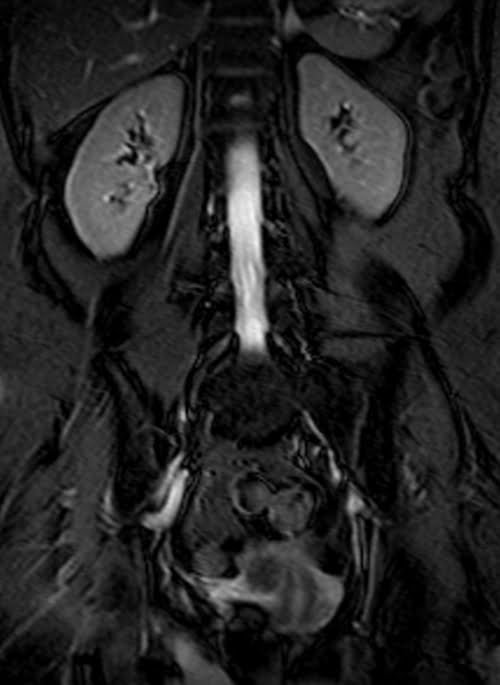

MRI kidney ureters and bladder( KUB) T2 TrueFISP fat saturated coronal images